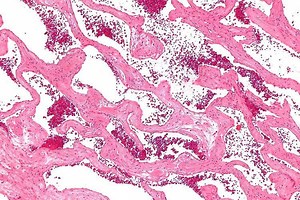

Cavernous Angioma 的热门建议 |